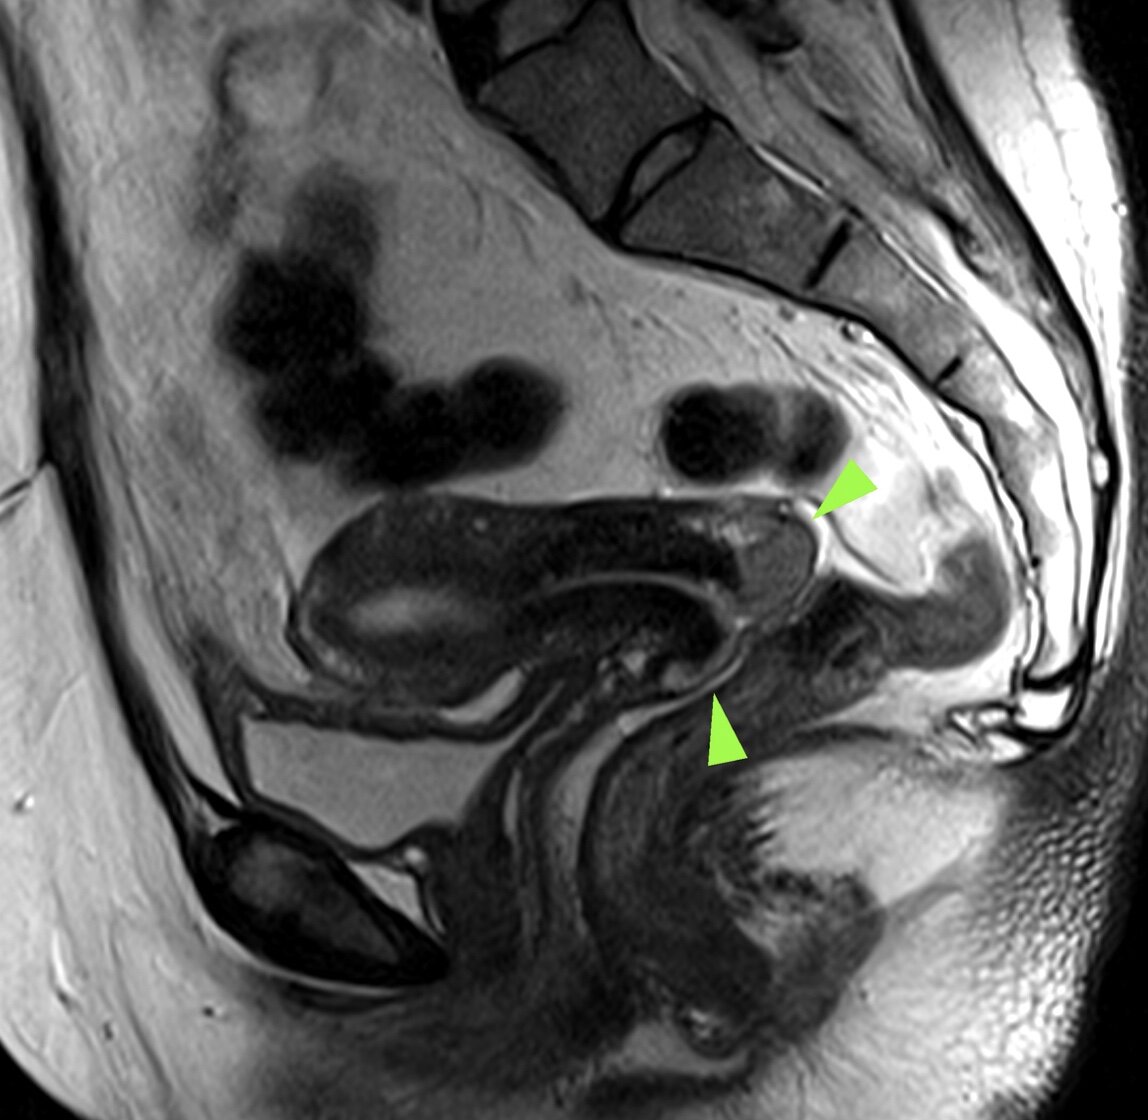

У нашей пациентки на МРТ определяется опухоль шейки матки размером ≈ 30*15 мм, без глубокой инвазии, что на первый взгляд укладывалось в I стадию (T1b).

Всё бы было относительно благоприятно, но внимательно оценив регионарные лимфоузлы... к сожалению, обнаруживаю несколько увеличенных, изменённых узлов в правой подвздошной области, которые так же как и образование шейки, замедленно копят контраст:

В заключении выставил предварительную стадию (на основании данных МРТ): T1bN1Mx IIIC1.

Что локально сама опухоль небольшая, её рост соответствует 1 стадии (Т1b), но выявлены метастазы в л/у (N1), и таким образом стадия сразу оказывается третьей (IIIC1).